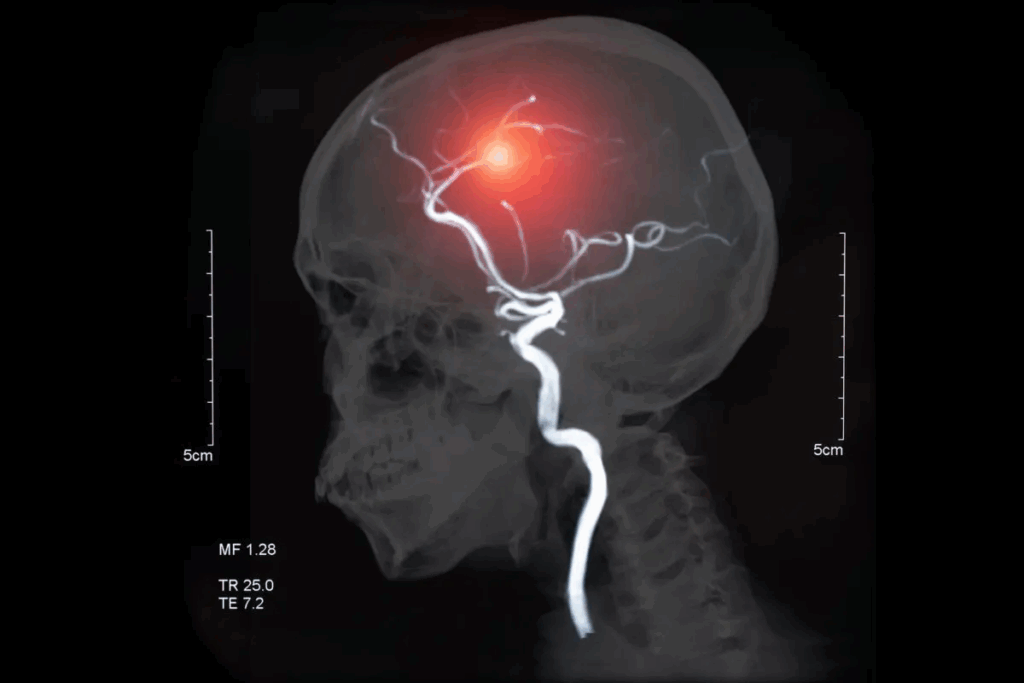

When a brain aneurysm is diagnosed, patients look for safe and advanced treatments. At Liv Hospital, we use a minimally invasive approach called brain aneurysm endovascular coiling. This method uses platinum embolism coils to stop blood flow to the aneurysm, preventing it from rupturing.

Our team of experts uses a small catheter to reach the aneurysm. They thread it into an artery and place coils or stents to hold the aneurysm in place. This endovascular coiling procedure is a groundbreaking option for treating aneurysms. It’s a less invasive choice compared to traditional surgery.

Endovascular coiling is a new way to treat brain aneurysms. It’s less invasive than old surgery methods. Doctors use it to fill the aneurysm with coils to stop it from bursting.

Coil embolization, or endovascular coiling, uses platinum coils to stop blood flow in aneurysms. It aims to prevent the aneurysm from bursting by blocking it and causing it to clot.

Imaging is key before coiling. We use digital subtraction angiography (DSA) and 3D rotational angiography. These help us understand the aneurysm’s shape, size, and where it is.